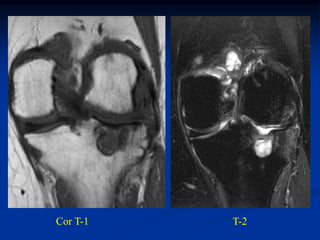

Case #636.1             Chondroblastoma with ABC

21 yr male with left hip pain for 4 mos.

Axial CT

scans

Cor PD   Gad

Axial T-1               T-2

T-2   Gad

PO bone graft